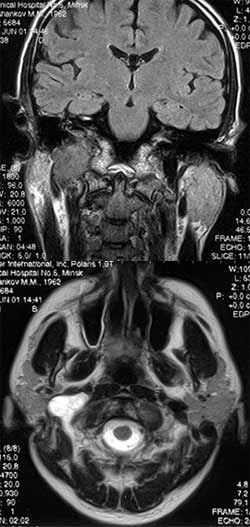

Рис. 3. МРТ. Опухоль яремного отверстия справа.

Новости лучевой диагностики 2002 1-2: 28-29